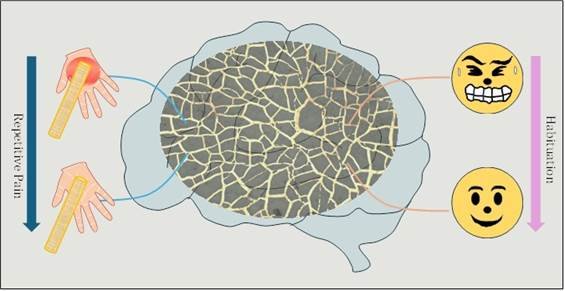

Using silver wire network on a stretchable material, scientists have developed a device that senses strain, mimics pain perception and...